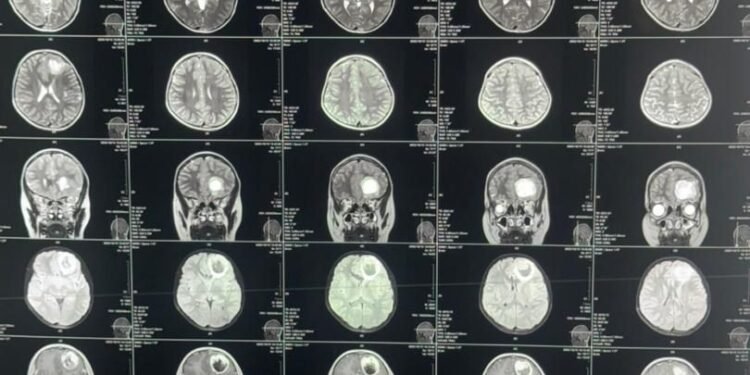

طالبان ساغلیقنی سقلش وزیرلیگی بوگون یکشنبه ۷- جدی، بیانات نشر قیلیب، بلخ حوزوی کسلخانهسی (ابوعلی سینا کسلخانهسیده) مییه تومورینی آلیب تشلش عملیاتی موفقیت بیلن عملگه آشیریلگنیدن خبر بېردی.

بیاناتگه کۉره، مذکور عملیات ایلکبار بلخ حوزوی کسلخانهسیده عملگه آشیریلگن.

اوشبو عملیات ۱۲ یاشر بیر قیز باله مییهسیده عملگه آشیریلگن.

طالبان ساغلیقنی سقلش وزیرلیگی، مذکور عملیات بیش ساعت دوام اېتگنینی هم معلوم قیلدی.

عملیات بۉلگن قیز باله، مییه توموری باعث آغیر باش آغریغی، کۉنگیل اَینیشی و کۉریش قابلیتی آزهیشیگه دوچ اېکن.